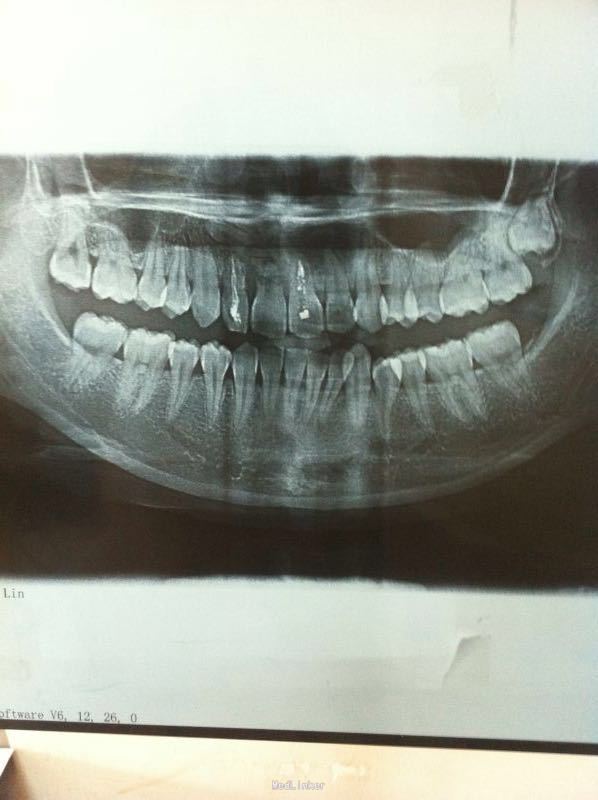

女22岁主诉:咬合不适,要求整牙。病史:患者自幼错合,近期咀嚼时颞颌关节疼痛,来诊。

查体:下颌牙列左偏,中线不齐,#12、#21做过根管治疗。

诊断:错合畸形。治疗:进行牙科正畸治疗。添加病种:口腔正畸。